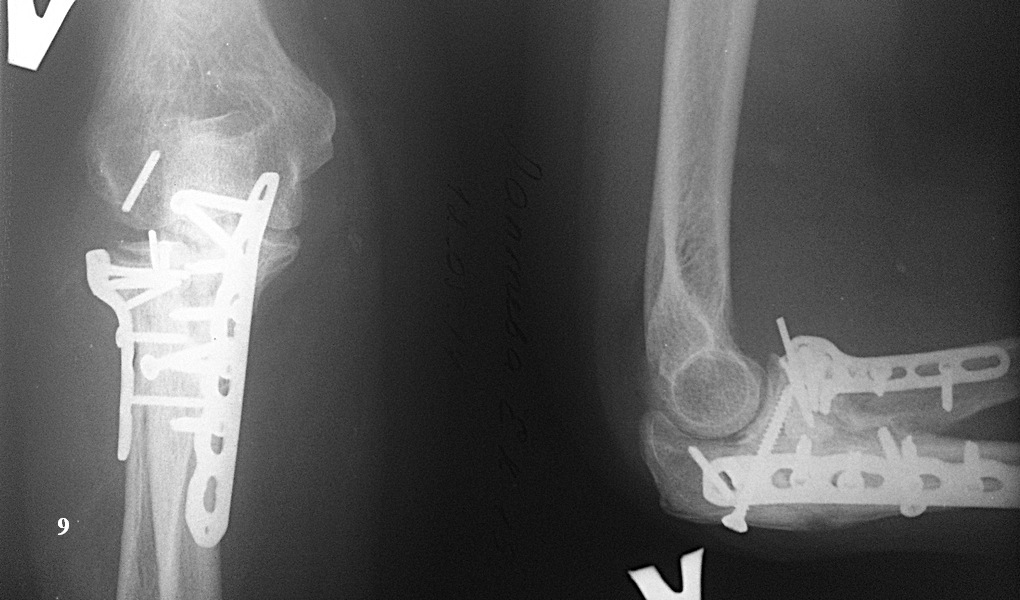

Казалось бы все счастливы, но в середине мая этого года (6 месяцев после операции) со слов больной: "Сидела на кресле, ничего не делала. И тут "щелк" в локте, с болью и легким хрустом при ротации предплечья". На снимке (рис. 10) перелом блок. винта из пластины на головке луча и миграция оставленной спицы. Скиаграмма для наглядности (рис. 11). Посоветовали ограничить движения, обезболивание. и сделать контроль через 3 недели.

Через три недели (7 месяцев после операции) вот такая картина (рис. 12). Блок. винт нашел свою "гавань" и затормозил возле локтевого отростка снаружи. А вот спица продолжает путешествовать и полностью вышла из головки в сторону наружной поверхности локтевого сгиба (рис. 13). При этом боли ушли, хруста нет, объем движений вот по этой ссылке: http://youtu.be/S4JK_Gpzaos